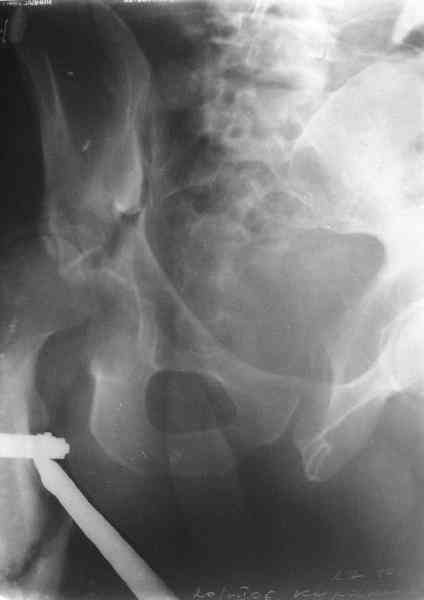

Уважаемы коллеги! Поступил непростой больной 24 лет через 1 месяц после травмы (фото в приложении). Кроме перелома правой вертлужной впадины, перелома и вывиха этого же бедра имеются переломы диафиза правой плечевой кости, диафиза правой локтевой кости, диафизов обеих костей левого предплечья.

Неврологии со стороны нижних конечностей нет. Планируем первым этапом выполнить ЗИМО длинных трубчатых костей. Вопросы: 1. имеет ли смысл в эти сроки идти на остеосинтез вертлужной впадины и вправление вывиха или планировать первичное эндопротезирование? 2. Есть у кого-нибудь ссылки или другая информация по поводу исходов лечения переломов вертлужной впадины, сопровождающихся вывихом головки бедра в разные сроки (буду очень признателен, если поделитесь)?A male 24 y.o, admitted to our unit today 1 month post injury - images attached. Except ipsilateral acetabular fx, femoral shaft fx and hip dislocation also he has shaft fxs of right humerus and ulna, left radius and ulna. No neurological deficits after the hip dislocation. At first we plan closed nailing of all long bones. Questions are regarding the acetabular fx + dislocation. With the 1 month of exposition and obvious callus everywhere does it make sense to attempt ORIF of the acetabulum with hip reduction, or primary THA should be considered? Does anybody have references on outcomes after delayed surgeries for acetabular fx + hip dislocation depending on duration of the delay? С уважением Максим Агалаков, УНИИТО Е-бург.

Now, to my own opinion. I believe that this is a Transverse + Posterior wall fracture type.

The transverse element does not seem so much displaced, and now after 1 month I believe it will be extremely difficult to mobilize and reduce. So I suggest you get a CT to check for incarcerated fragments, a high possibility in this unreduced dislocation. Then you open posteriorly, Kocher Langenbeck, with the patient prone, extract any incarcerated frgments, reduce the hip, fix the posterior wall by screws, and then apply a contoured reconstruction plate from the iliac wing to the ischium. This plate will hold the ransverse element, as well as buttress the posterior wall fragment(s).